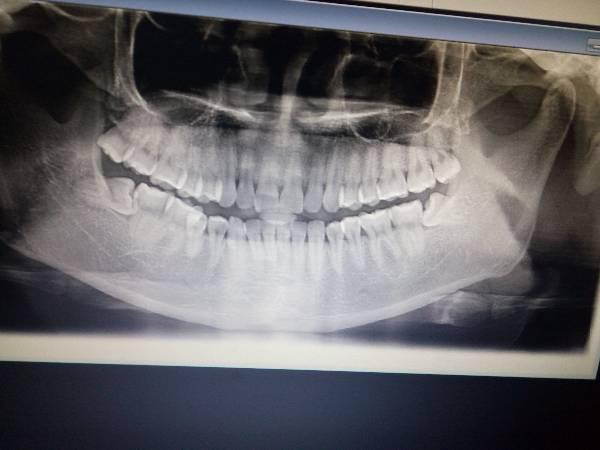

口腔牙片拍摄技巧

口腔牙片拍摄技巧,牙科小牙片机拍片技巧

下颌阻生智齿,口腔医院拍了牙片,这种难度大不大?看网友好多需要缝

格伦菲尔口腔(民治店)我的牙片图片 - 第16张

拍的牙片

为什么要拍牙片?